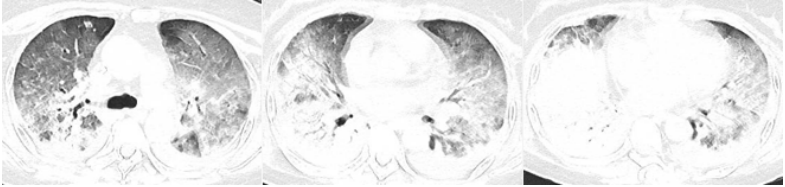

患者,女,50岁;活动后喘息20天,加重伴发热3天,2021年11月19日转入我院。入院胸部CT显示:双肺实变,磨玻璃影(图1)。11月24日复查胸部CT可见病变进展迅速(图2)。予患者气管插管机械通气、俯卧位等,呼吸衰竭未见改善。遂于11月25日启动VV-ECMO(转速2860 rpm,流量4.5 L/min,氧浓度100%)。追问病史:患者入院前1月有活动后气促症状,自觉全身不适,近2年有眼干、口干不适。进一步检查发现,ANA反应阳性(+),ANA核型为胞浆颗粒型(异常);抗SSA/Ro抗体阳性(++)、抗Ro-52抗体阳性(+++)。诊断:急性间质性肺炎(AIP);Ⅰ型呼吸衰竭;混合性结缔组织病。治疗:VV-ECMO+呼吸机辅助通气+俯卧位通气、激素(甲强龙80 mg×7天,60 mg×3天,40 mg qd)、免疫抑制剂(环磷酰胺400 mg qd×3天)、抗感染(哌拉西林他唑巴坦4.5 g q12h+莫西沙星0.4 g qd+氟康唑氯化钠注射液20 mg qd)、抗凝等。在随后的一段时间内,患者影像学改善不明显(图3)。直至12月20日,复查胸部CT可见患者肺部病变较前明显吸收(图4)。2021年12月31日VV-ECMO撤机后,继续气切呼吸机辅助通气,甲强龙40 mg qd抗炎治疗,继续抗感染治疗,2022年1月7日脱机,1月21日气管封管,1月26日出院。后续治疗:强的松25 mg qd,环磷酰胺600 mg q2w×4次,序贯吗替麦考酚酯0.5 g bid。重症间质性肺疾病(ILD)在诊断方面需要考虑以下问题:是ILD吗?是哪种ILD?严重程度如何?在治疗方面,除了生命支持(呼吸支持重点)和病因治疗,并发症的处理也至关重要。重症ILD的诊断包括两方面,一方面是通过影像学、病史+临床表现、BALF-NGS、实验室检查、肺活检等对ILD进行诊断;另一方面涉及重症,患者多面临呼吸衰竭甚至多器官衰竭,因此时间更加紧迫。在ICU内最常见的重症ILD包括:特发性肺纤维化急性加重(AE-IPF)、自身免疫相关性ILD、肿瘤治疗相关性ILD、隐源性机化性肺炎(COP)、AIP、过敏性肺炎(HP)、急性嗜酸性粒细胞性肺炎(AEP)、药物相关ILD等。在影像学方面,最易导致重症的类型有弥漫性磨玻璃影和实变影。最常见的鉴别诊断就是重症肺部感染。表现为弥漫性磨玻璃影或实变影的ILD较为多见,例如:HP、嗜酸性粒细胞性肺炎(EP)、结缔组织病相关间质性肺病(CTD-ILD)、非特异性间质性肺炎(NSIP)、脱屑性间质性肺炎(DIP)、淋巴细胞性间质性肺炎(LIP)、机化性肺炎(OP)、AE-IPF、肺泡蛋白沉积症(PAP)、肺泡微结石症、结节病、弥漫性肺泡出血综合征、肺水肿等。而很多感染性疾病影像学也可表现为磨玻璃影,例如:卡氏肺孢子菌肺炎(PCP)、病毒性肺炎、巨细胞病毒性肺炎、支原体肺炎。尽管如此,ILD也有部分影像学具有特征性,可以被识别。图5左表现为肺陷闭,也称为“猪头肉冻征”,这是典型的亚急性HP的影像学特征。图5右表现为弥漫性磨玻璃影,但以肺门向外扩展,外面有肺大泡,这是典型的PCP表现。临床上多见自身免疫性疾病导致的ILD,此类疾病也具有共同的特征,例如双肺弥漫,病理方面以NSIP或OP为主要特征。但也有部分患者可以出现弥漫性肺泡损伤(DAD)特征。如图6所示,左图为ANCA相关性血管炎,右图为MDA5相关性间质性肺病。因此,一定要警惕容易发生这种病理改变的自身免疫性疾病。